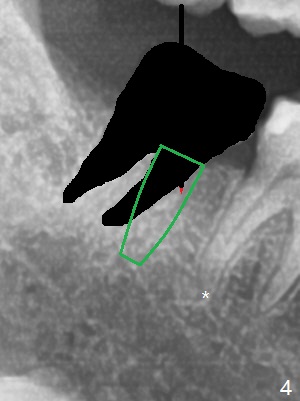

A 43-year-old woman will return for #9 and 31 implant placement. To prevent periimplantitis, a smaller implant will be placed deeper at #9 (3.8 or 4.1x14 mm) vs. 4.5x14 mm at #8 (2 years post cementation). The same type of implant (easy cement removal vs. the one at #4 (4.5x17 mm; 2 years post cementation)) will be placed at #31 mesial socket (Fig.2-4: 4.5x8.5 or 10 mm, never pass beyond the distal apex of the tooth #30: *). In fact, the tooth #9 is salvageable. Finally the patient decides to work on the tooth #12 (the same implant as #4). Take photos to show the residual roots. If there is buccal plate atrophy, prepare for socket shield.